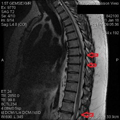

I’m not gonna give you guys a lesson in reading MRI Reports, so here’s the short version. (T# are different vertebrae – Google it)

T5-T6: 4 mm disc protrusion

T6-T7: 10-11 mm disc protrusion

T7-T8: 9 mm disc protrusion

T8-T9: 3-4 mm disc protrusion